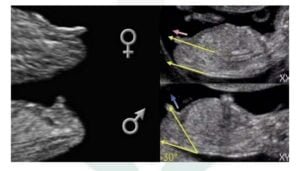

Ao pegar a imagem do seu ultrassom de 12 semanas, observe o falo do bebe. O falo refere-se ao início do desenvolvimento da genitália externa do bebê durante o desenvolvimento embrionário. A partir da décima segunda semana de gestação já se pode ter uma previsão de mais de 90% no sexo do bebê.

Quando o falo está para frente, temos 90% de chances de ser uma menina. E quando o falo está para cima temos 90% de chances de ser um menino.

Observe a imagem abaixo:

No caso de um feto masculino, os testículos começam a secretar hormônios masculinos, como a testosterona, que influenciam o desenvolvimento do falo do feto em um pênis e outras estruturas genitais masculinas. Por outro lado, em um feto feminino, a ausência de altos níveis de hormônios masculinos levará ao desenvolvimento de genitais femininos, como o clitóris e os lábios vaginais.